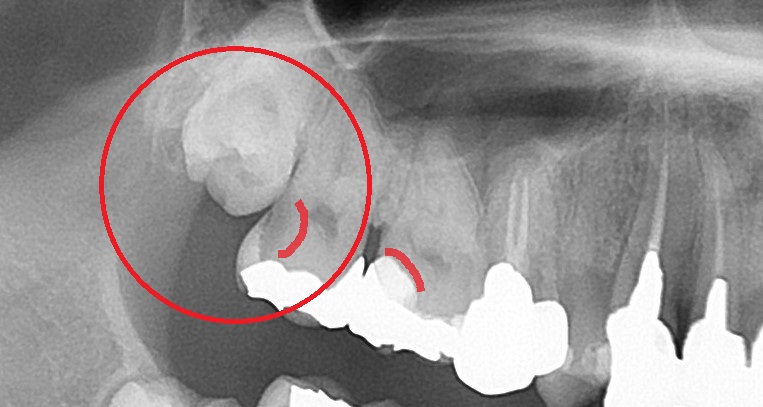

エックス線写真で、銀歯内部の虫歯を認めます。

エックス線写真は歯の見えないところが見えてきますので、

歯の内部にむし歯があるのが分かります。

親知らずがあるのも分かります。

そして、親知らずが当たっている手前の歯がむし歯になっています。

むし歯になると、歯の内部が溶けてくるので、エックス線写真で黒く抜けた像ができます。

赤く囲まれた歯が上の親知らずで、

赤くマーキングしてある箇所にむし歯があります。